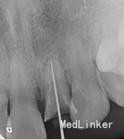

2.一次性根充后临时桩冠修复,观察两周。

感谢分享~资料图片比较完善,试尖片和根充片都有。目前临床多采用纤维树脂桩核修复,在充分考虑剩余牙体组织抗力的前提下,要尽可能扩大桩核的粘结面积